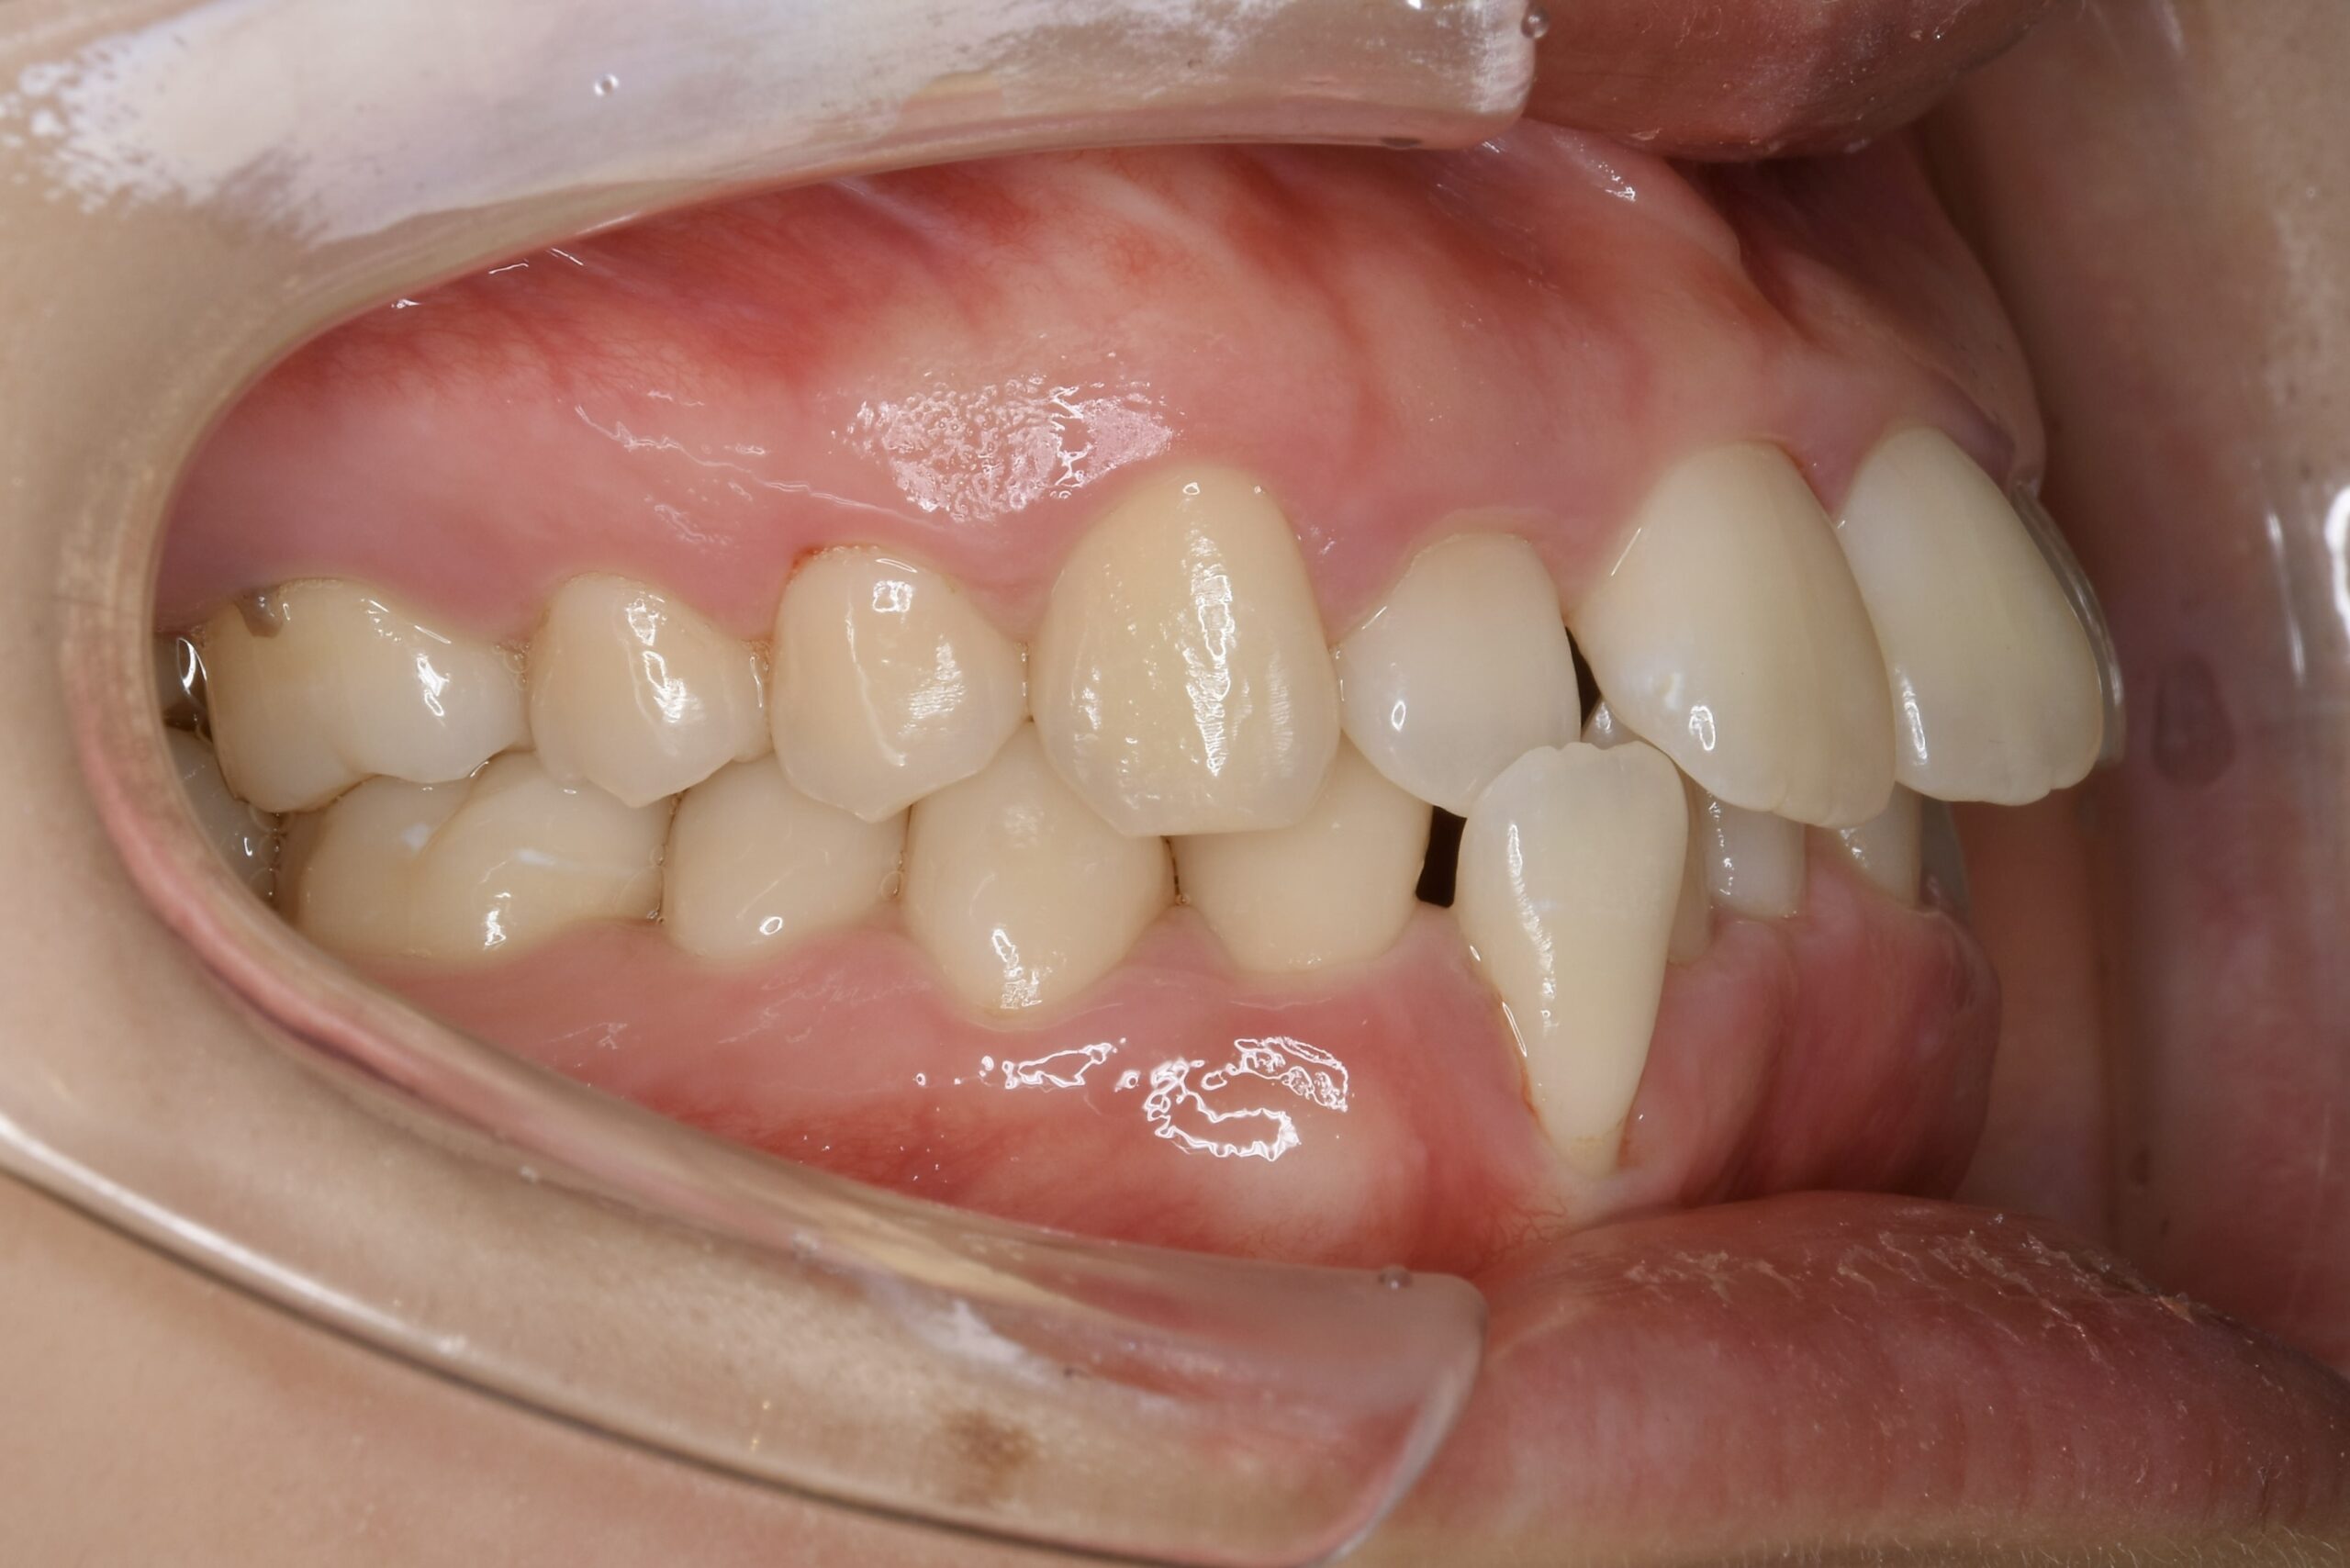

21歳 女性 治療期間:1年1ヶ月

叢生(ガタガタ)

マウスピース矯正装置(インビザライン)

BEFORE

AFTER

主訴

周りの人の歯並びが綺麗で自分の歯並びを治したくなってきた。

診断名・主な症状

叢生

治療内容

上下とも歯並びの横幅を広げながら、でこぼこを解消しました。

マウスピース矯正(インビザライン)

抜歯あり(智歯抜歯)

治療期間

1年1ヶ月

通院回数

10回

費用

85万円程度(税別)

リスク・副作用

痛み、歯肉退縮、歯根吸収、抜歯に伴う出血や腫れが生じることがあります。